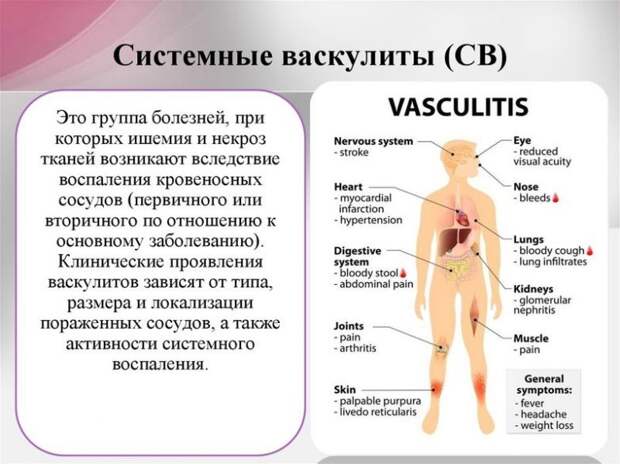

Васкулит – серьезное заболевание сосудов, причины которого до сих пор остаются загадкой для современной медицины. При обострении воспаляются стенки вен и капилляров, нарушается кровоснабжение внутренних органов.

Проблема имеет обширную классификацию, делится на первичную и вторичную форму.

Заболевание относится к аутоиммунным и мало изучено врачами. Оно связано с воспалением кровеносных сосудов, может затрагивать крупные вены и мельчайшие капилляры. Среди возможных причин обострения

На начальной стадии заподозрить опасное заболевание сложно: у больного поднимается температура, он быстро устает, жалуется на головные боли. Симптомы легко принять за проявление ОРВИ, гриппа или переутомление на работе. В это период воспаление затрагивает внутренние органы, стенки желудка или кишечника.

сыпь покрывает кожу конечностей, грудь и шею; во рту появляются болезненные язвочки; активно выпадают волосы, ногти становятся ломкими.При васкулите высыпания и мелкие кровоподтеки возникают не только на коже: они покрывают слизистые оболочки органов. В зависимости от места воспаления у больного появляются симптомы более опасных заболеваний:

Нарушение пищеварения, стул с кровью, тошнота и болезненные спазмы в животе при поражении кишечника.

Отечность, боль в пояснице, высокое давление при воспалении капилляров в почках.

Одышка, тахикардия, обморок при поражении крупных сосудов сердца.